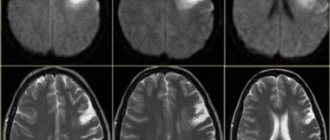

МРТ головного мозга

При умеренной и тяжелой ишемии мозга часто применяют магнитно-резонансное исследование его структур. При легкой ишемии, проходящей в течении суток, редко возникает необходимость в МРТ.